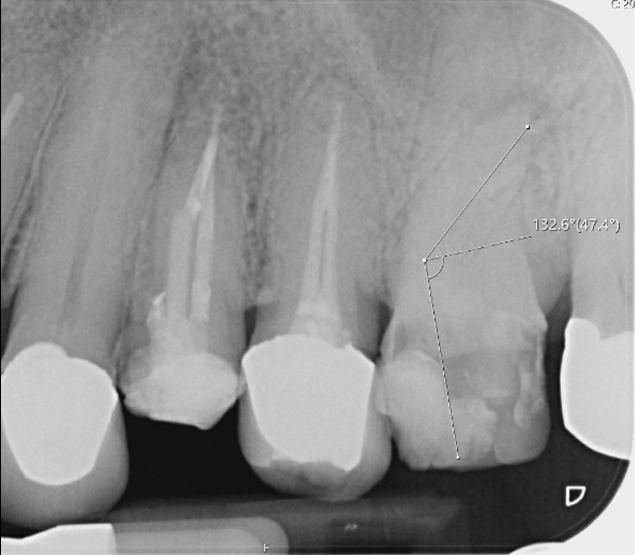

Root canal retreatment and bypass of separated instrument

Pre-op

12 month review demonstrating healing